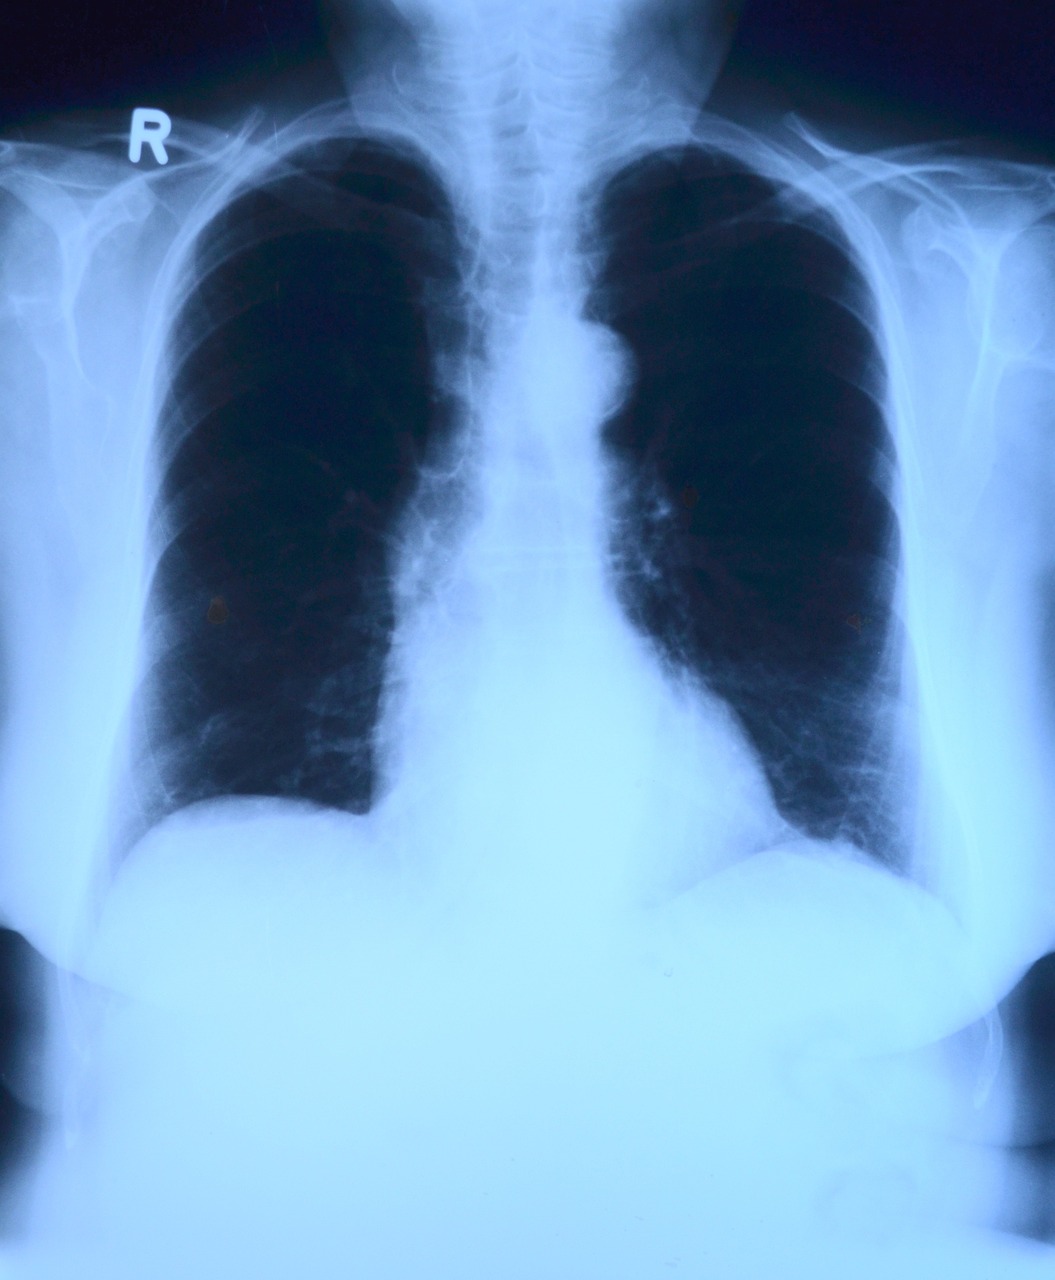

1. 폐암검진이 중요한 이유 – 중년 남성의 가장 치명적인 암

폐암은 국내 암 사망률 1위 질병입니다. 특히 **중년 이상 남성**에게는 사망률이 더욱 높습니다.

그 이유는 간단합니다. ✅ 자각 증상이 늦게 나타나고 ✅ 진단 시 이미 말기로 진행된 경우가 많으며 ✅ 흡연 경력이 길어질수록 위험이 급격히 상승하기 때문입니다.

폐암은 조기 증상이 거의 없기 때문에 ‘조용한 암’이라고 불립니다. 하지만 일부 초기 징후를 인지하고 있으면 자각 증상만으로도 조기 검진의 계기를 만들 수 있습니다.

이러한 증상 중 2가지 이상이 지속된다면 건강검진 대상자 여부와 관계없이 흉부 X-ray 또는 저선량 CT 검사를 받는 것이 좋습니다.